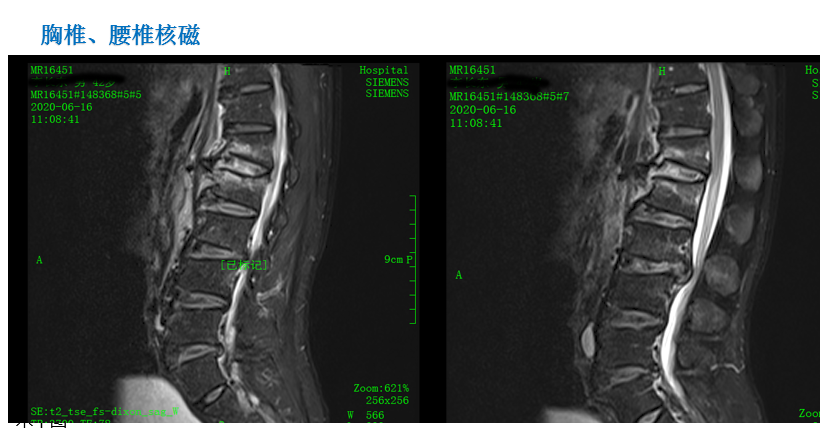

影像资料:

诊 断:

1:腰1、2椎体压缩骨折(椎体分别压缩约40%、10%);

2:腰椎退行性改变伴椎管狭窄;

3:腰3/4、4/5、腰5/骶1椎间盘膨出;

4:右跟骨骨折;

5:胸12陈旧性骨折。

治疗方案:

1:腰1、2椎体骨折复位内固定术,右跟骨骨折切开复位内固定术。

2:腰1、2椎体骨折复位内固定、腰3/4椎间盘摘除椎间融合内固定术,右跟骨骨折切开复位内固定术。

术后影像: